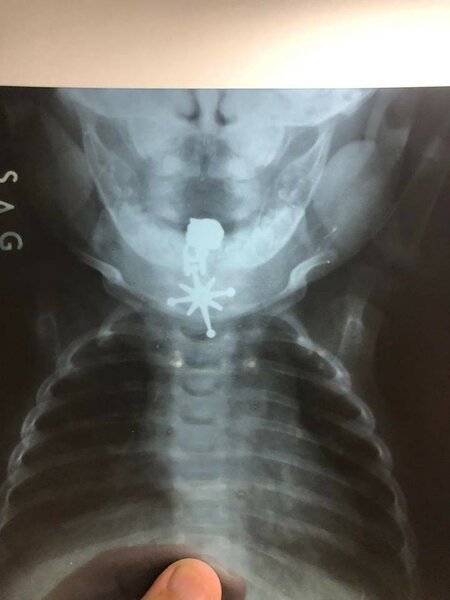

ARANTV.AZ bildirir ki, Unikal.org-un əldə etdiyi məlumata görə, Salyanda 5 aylıq Sevinc Məmmədova zəncirbəndin üzərində olan ulduz formalı qıfıllıcanı ağzına götürüb. Bu zaman udduğu qıfıllıca onun tənəffüs yolunda ilişərək qalıb. Çarəsiz durumda olan azyaşlının valideynləri onu paytaxtda yerləşən 1 saylı Kliniki Tibbi Mərkəzə gətiriblər. Cərrah Allahverdi Musayev körpəni əməliyyat edərək onun tənəffüs yolunda qalan qıfıllacı çıxarıb. Hazırda Sevinc Məmmədovanın vəziyyəti stabildir.